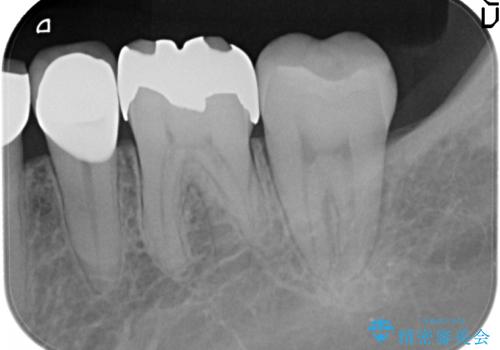

- 奥歯に以前充填した部分に時折知覚過敏があり改善を希望され来院されました。

長期的にみて劣化の早いコンポジットレジンを除去後、しっかりと噛んでいる歯なのでセラミックに比べ壊れたりかけたりすることの少ないゴールドで修復する計画を立てます。